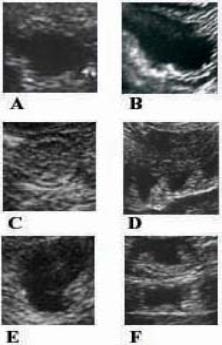

Duodenal (A-B) and Colonic (C-F)

imaging